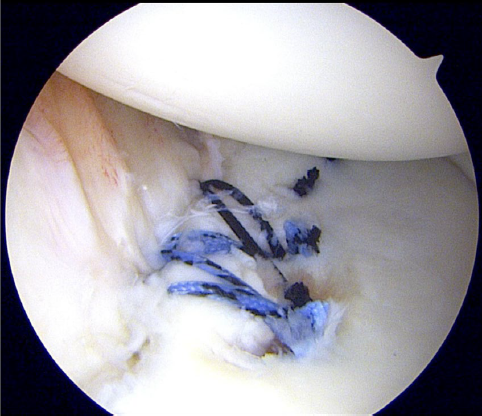

一般的な鏡視下Bankart修復術では、剥がれた関節唇を「点」で縫い合わせることが多いですが、当院が提供するDAFF(Double Anchor Footprint Fixation)法は、靭帯を関節窩(肩の受け皿)の「面」に固定します。

- 面での強固な固定: 前下肩甲上腕靭帯(AIGHL)を広い範囲で骨に密着させることで、より生理的な修復と強固な安定性を実現します。

- 最新デバイスの活用: Smith & Nephew社の「マイクロラプターノットレス」などの最新アンカーをいち早く導入。挿入時のトラブルを回避し、1mm単位の精度を保ちながら手術時間を短縮します。

1mmの精度が、アスリートの未来を変える

「手術は、関節の機能を守り、残すためのもの」 私たちは、関節鏡視下の極めて小さな傷から、コンマ数ミリの精度で靭帯の位置を整えます。そのこだわりが、術後の違和感を減らし、以前と変わらないパフォーマンスの発揮を可能にします。